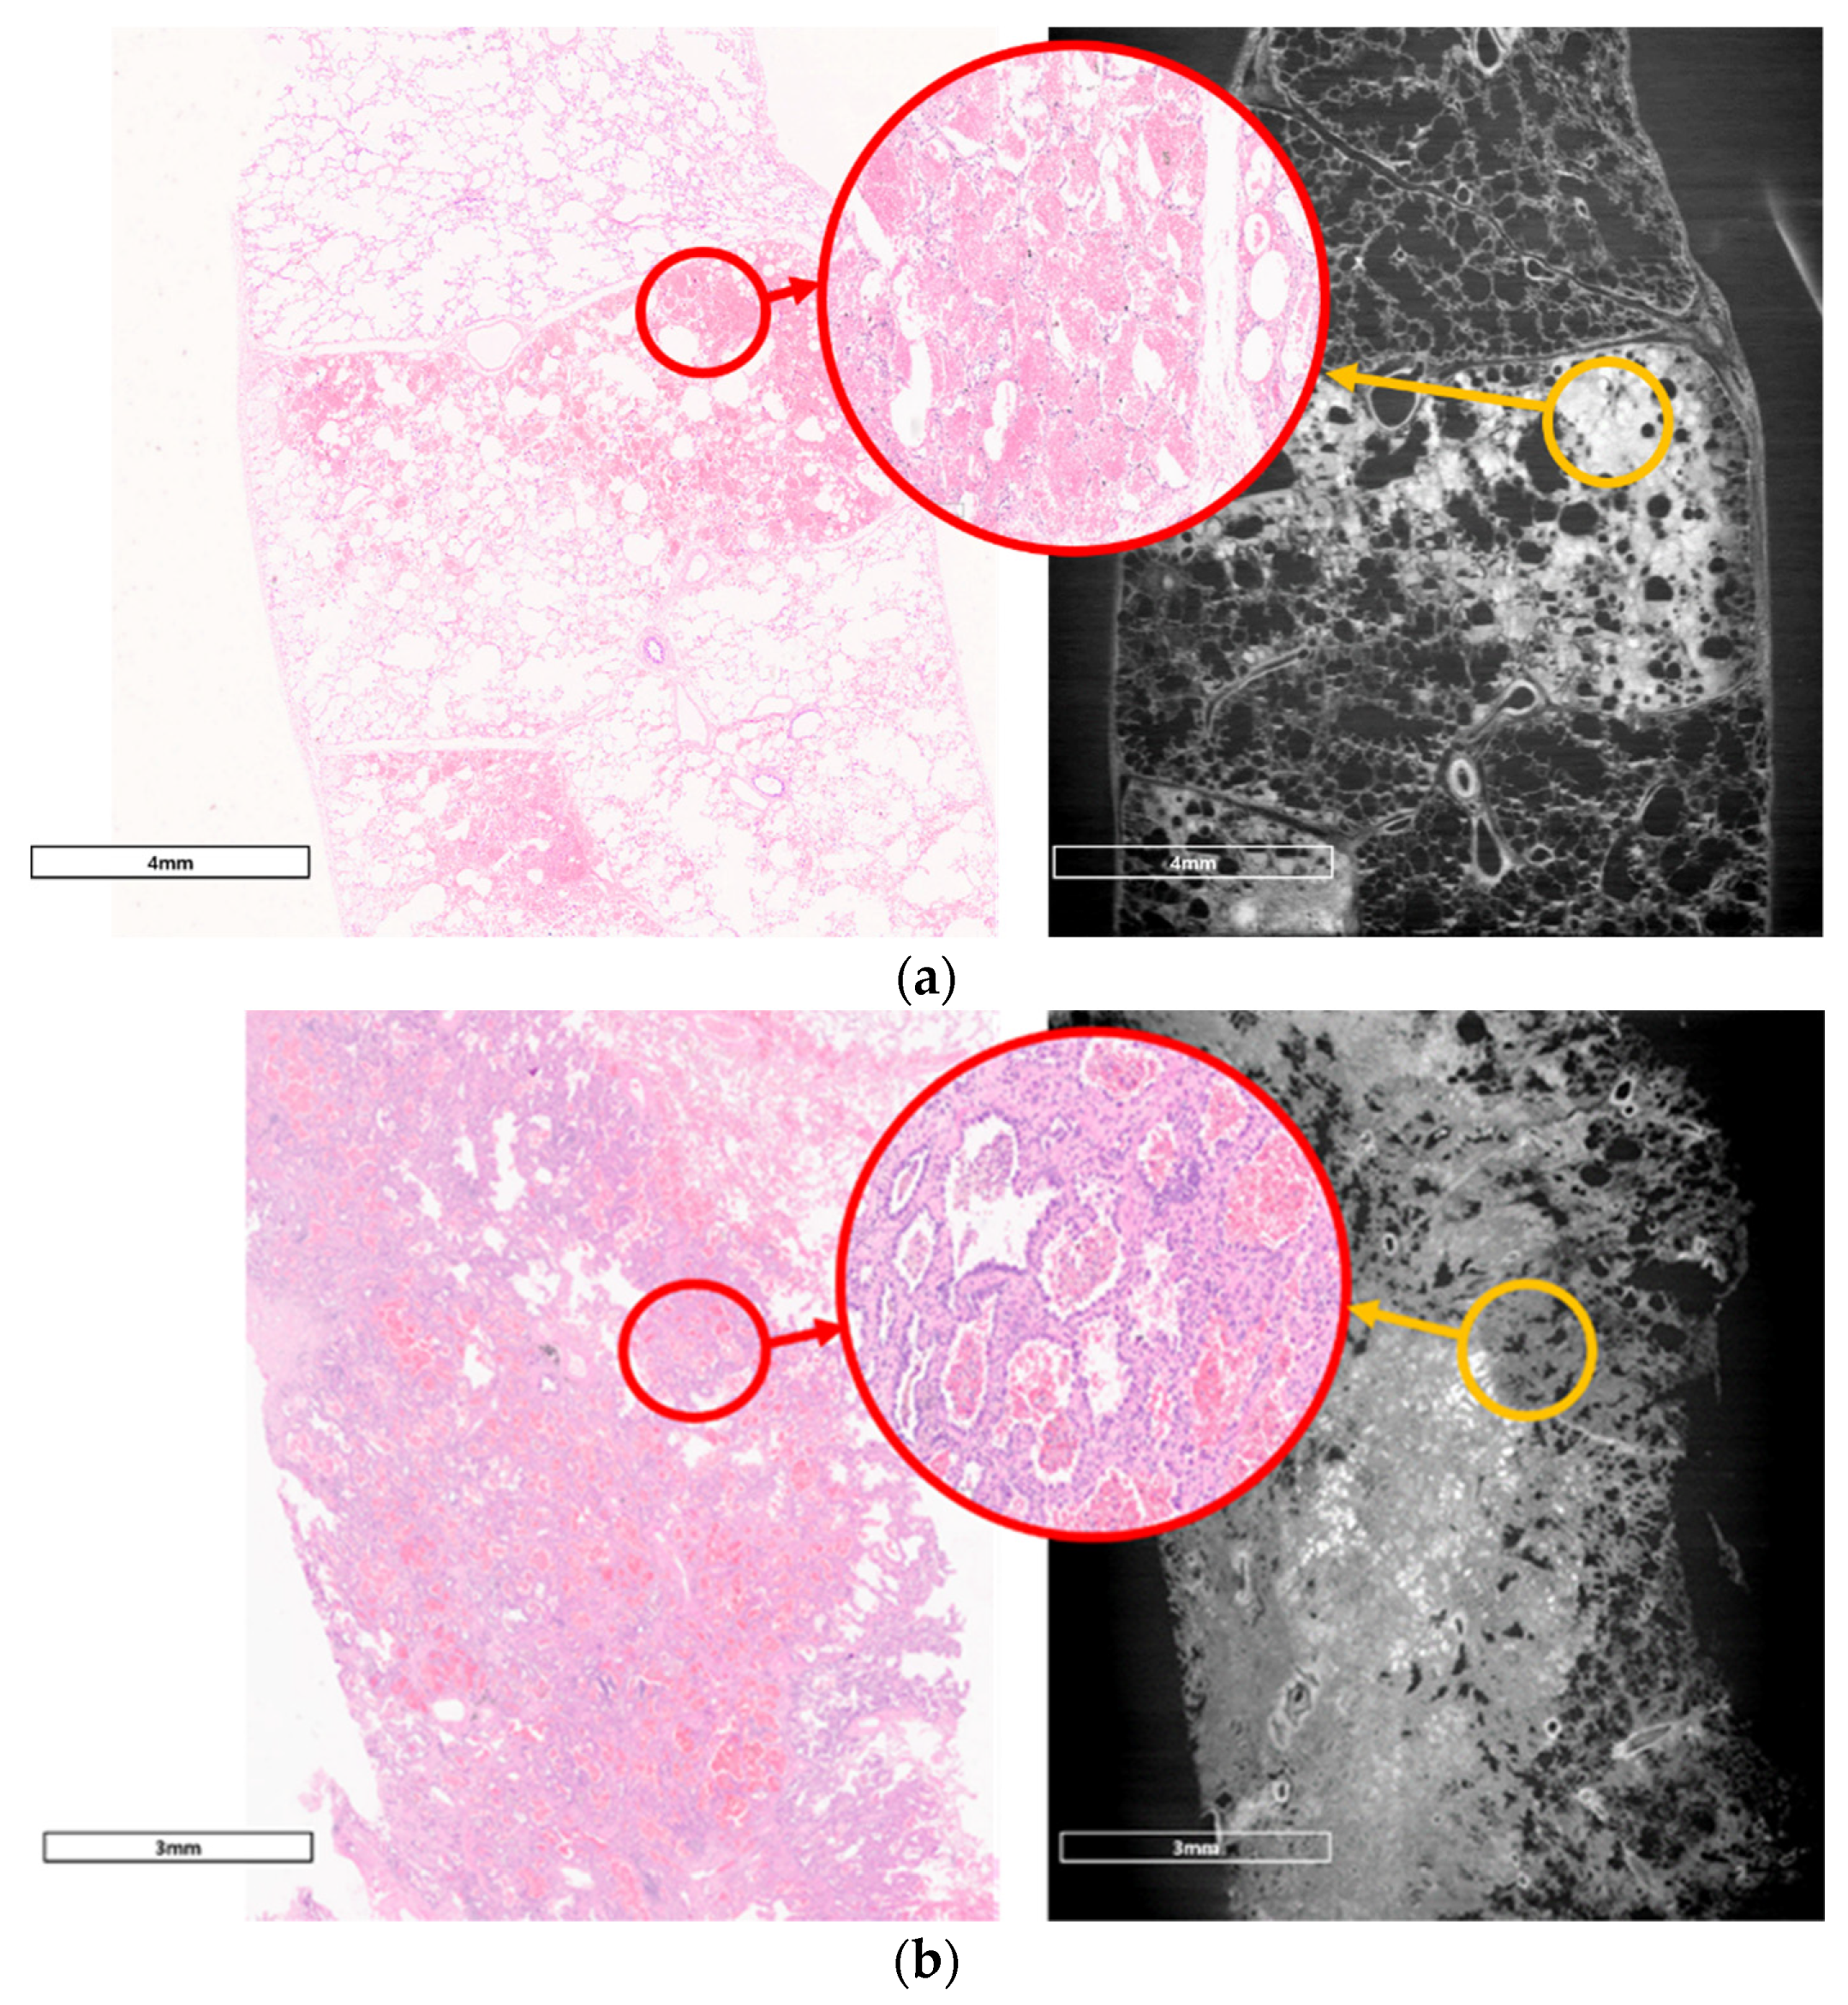

3.1. Refraction-Contrast Synchrotron Tomographic Images of Lung Tissue Including Cancer and 3D Reconstruction

3.2. Comparison with Pathologic Examination